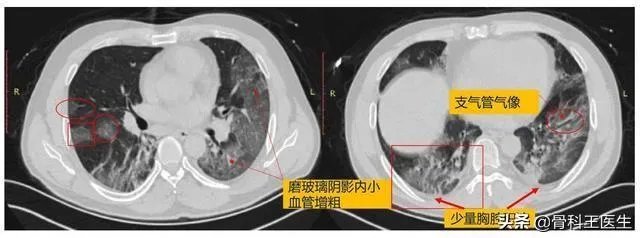

上图总结了新冠病毒CT的典型影像学表现,这是在不断的认识中总结出来的经验。当我们对CT还不是很清楚的时候,也就是疫情初期,核酸检测一定是优于临床诊断的。

案例分享:

陈某,男,50。发热4天,T:38.2°C,伴干咳、乏力、胸闷;

流行病史:武汉地区,1.16从武汉乘火车返回,聚集性发病;

CT表现特点:1.23日CT示右肺上叶磨玻璃样渗出影,内见空气支气管影及增粗血管影;

1.26日CT示右肺病变明显增多、增大,新发左肺病变。

从病变早期到进展期,像这样一种典型的CT表现的疑似病例患者,我们就完全有理由确诊,在以前,如果核酸检测是阴性,那么这个病人仍然是疑似病例,这对这个病人是不公平的。